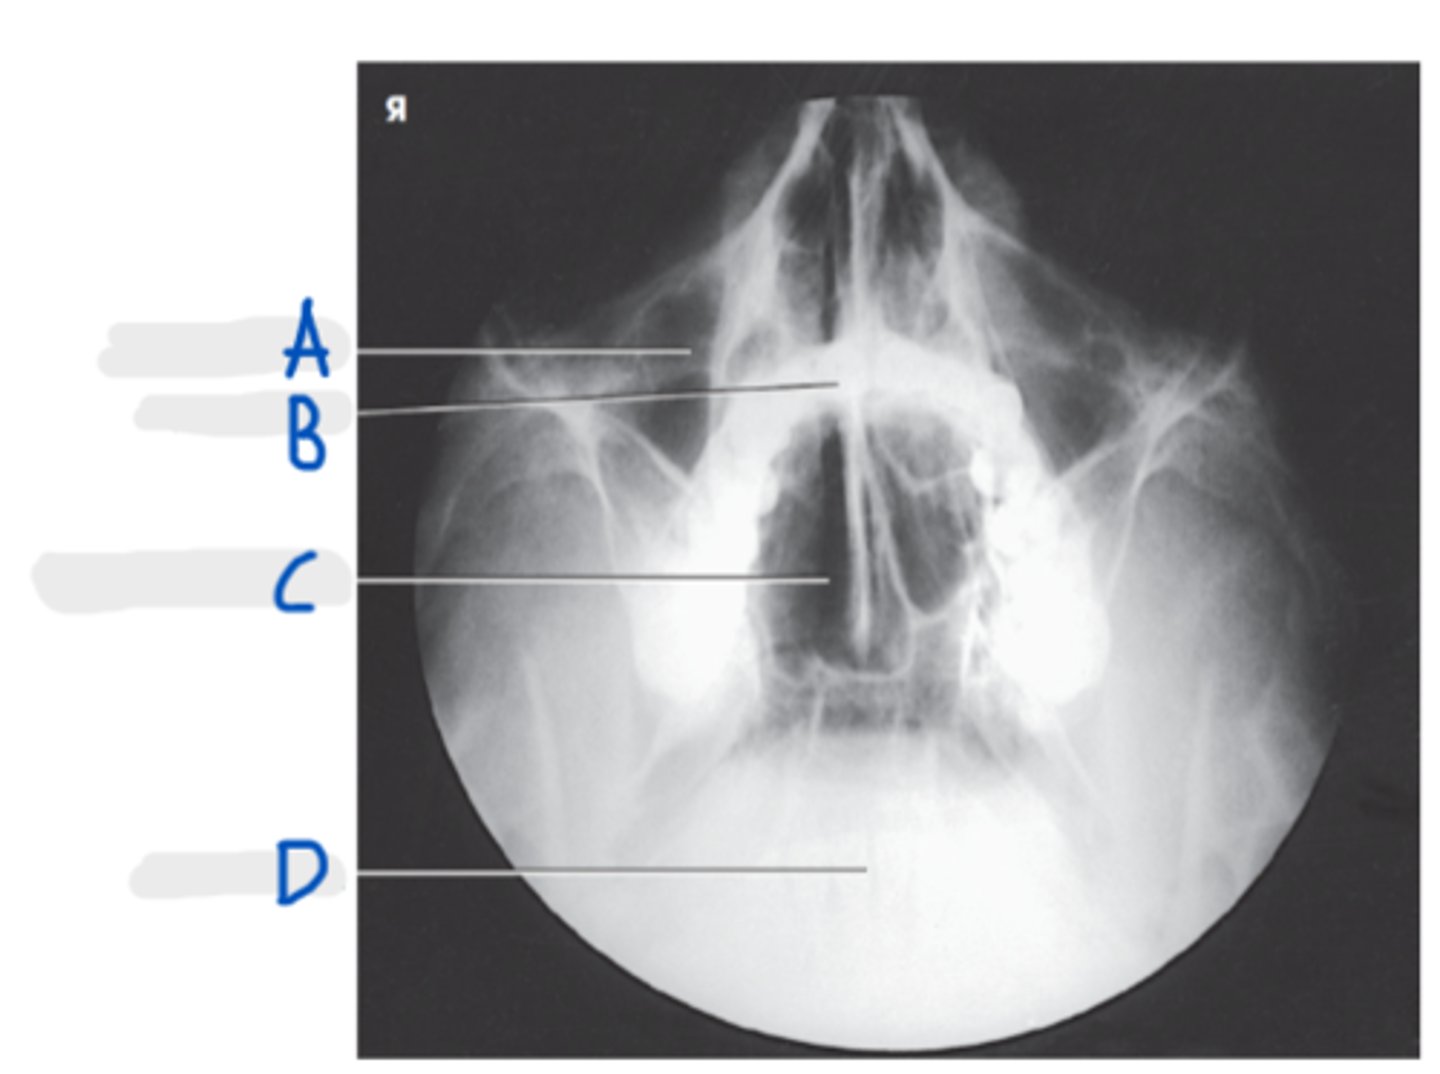

Maxillary sinus

A

Ethmoid air cells

B

Mandible

C

Sphenoid Sinus

D

Foramen spinosum

E

Mandibular condyle

F

Dens or odontoid process

G

Petrosa

H

Mastoid process

I

Occipital bone

J

Parietoacanthial (Waters Method)

What projection is this?

CR to exit at acanthion

What is the CR for the Parietoacanthial (Waters Method)?

MML perpendicular to IR

What line should be perpendicular to the IR on a Parietoacanthial (Waters Method)?

Maxillary Sinuses

What sinuses are best demonstrated on the Parietoacanthial (Waters Method)?

37 degree angle from IR plane

What angle should the OML be at for a Parietoacanthial (Waters Method)?

Equidistant lateral border of skull and lateral borders of the orbits

How do we look for rotation/tilt for the PA Caldwell or Waters?

Pretrous ridges lie inferior to maxillary floor

Where do the petrous ridges (pyramids) lie on a Waters radiograph?